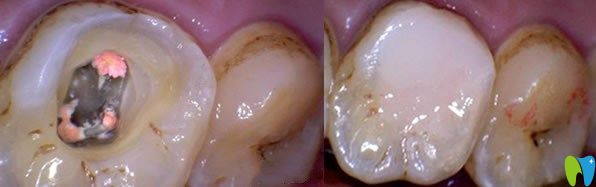

二、牙髓炎不治療會(huì)怎么樣?

牙髓炎是一種嚴(yán)重的制病因素,一旦發(fā)炎不能好轉(zhuǎn),不是吃了消炎藥就可以恢復(fù),牙髓炎持續(xù)惡化,繼續(xù)發(fā)展就會(huì)造成牙髓死亡。牙齒沒有得到及時(shí)的診治,久而久之,牙齦就會(huì)萎縮,牙齒就會(huì)變得稀疏松動(dòng),導(dǎo)致牙齒脫落。

急性牙髓炎不治療的后果